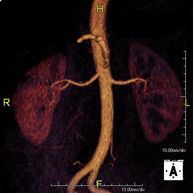

Prueba diagnóstica no invasiva que consiste en la obtención de imágenes de alta definición anatómica de todo el cuerpo mediante el empleo de un campo electromagnético y ondas de radio (con un emisor y un receptor). No utiliza radiación ionizante. Es una prueba muy importante en la búsqueda de metástasis en pacientes con neoplasia conocida. No requiere preparación previa. No es necesario el empleo de contraste paramagnético (Gadolinio). - Angio-RM Aorta abdominal

Prueba diagnóstica no invasiva que consiste en el estudio de la arteria aorta abdominal, obteniendo imágenes de alta definición anatómica mediante el empleo de un campo electromagnético y ondas de radio (con un emisor y un receptor). Es indispensable el uso de contraste paramagnético (Gadolinio). Sin embargo, no utiliza radiación ionizante. La calidad de las imágenes permite realizar reconstrucciones en 2D y 3D. Está indicado en aquellos pacientes con enfermedad vascular (aterosclerosis), estudio de aneurismas, en estudios pre-quirúrgicos de lesiones adyacentes a la aorta abdominal como "mapa" vascular, etc. - Angio RM Aorta-ilíaca

Prueba diagnóstica no invasiva que consiste en el estudio de las arterias renales, obteniendo imágenes de alta definición anatómica mediante el empleo de un campo electromagnético y ondas de radio (con un emisor y un receptor). Es indispensable el uso de contraste paramagnético (Gadolinio). Sin embargo, no utiliza radiación ionizante. La calidad de las imágenes permite realizar reconstrucciones en 2D y 3D. Esta prueba está indicada por ejemplo en aquellos pacientes que sufren de HTA refractaria al tratamiento, en pacientes con lesiones renales para tener un mapa "vascular" pre-quirúrgico, etc. - Entero-RM